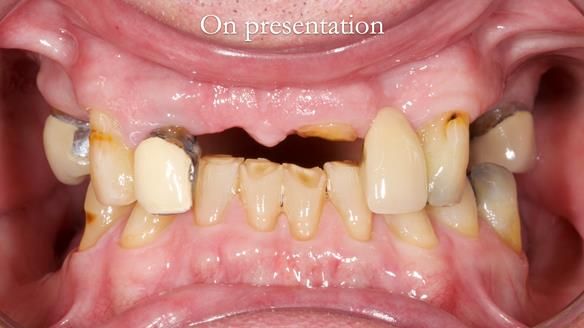

This edition features the case of Edgar, who sought help for a poorly fitting, acrylic-based partial denture that rocked, affected his speech, and caused discomfort. After considering various treatment options, including dental implants, Edgar opted for a metal-based removable partial denture, designed by myself with input from my technician, Rowan Garstang.

Treatment Process: I provided the clinical work while Rowan Garstang delivered the technical aspects. The treatment required fifteen visits to fit and review Edgar.